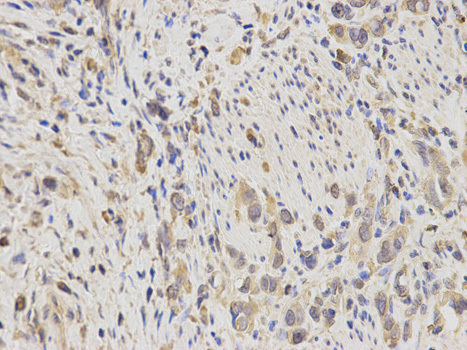

Supportive validation

- Submitted by

- OriGene (provider)

- Main image

- Experimental details

- Immunohistochemistry of paraffin-embedded human stomach cancer using IDE antibody at dilution of 1:200 (400x lens).